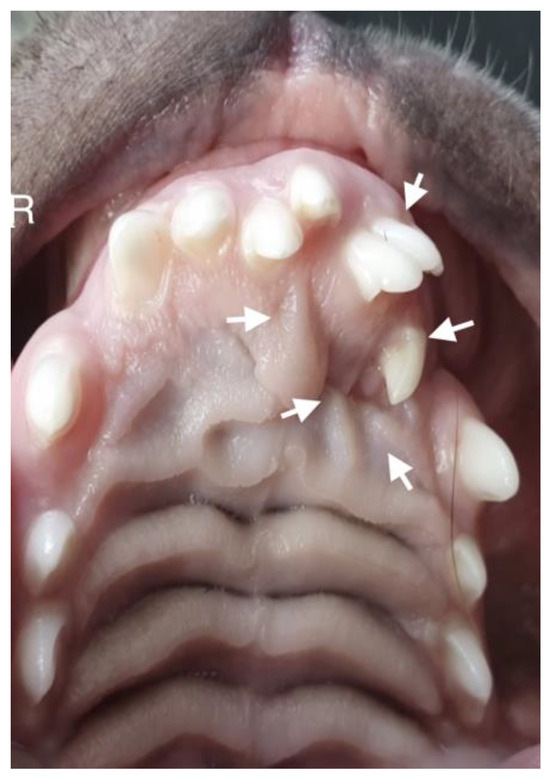

A 10-month-old American Staffordshire Terrier dog was referred for an orthodontic consultation due to abnormal alignment of the maxillary teeth and the resulting bite injuries. Clinical examination revealed three properly aligned incisors on the right side and four incisors (including one tooth with a double crown) on the left side arranged chaotically (Figure 7). Intraoral examination revealed an abnormal palatal crease in the projection of teeth 103–203 and a hard and painful protrusion about 3 cm in diameter on the left side. The roentgenogram showed the presence of three additional incisors, including two unerupted ones, growing in the opposite direction to the alveolar process. The double tooth on the X-ray appeared to be a fused tooth (tooth fusion occurs as a result of physical force or pressure on an adjacent tooth’s bud, leading to the contact of the two tooth buds and their fusion before calcification) [12]. The abnormal growth of the incisors on the left side caused pressure on the incisal bone, along with skewing of the nasal septum to the right side (Figure 8). The third incisor, along with an additional third incisor, showed radiographic features of a dentigerous cyst. A decision was made to perform open extraction of the ectopic teeth using the CLP method.

The bone cavity, after such a large open extraction, was 3.0 cm × 4.2 cm; so, the decision was made to implant polymeric hydroxyapatite with curdlan soaked in 0.9% NaCl into the areas of bone loss. The flap was sutured with 4-0 monofilament single sutures. A follow-up radiograph was taken 28 days after surgery. On clinical examination, the soft tissues were healed properly. On the follow-up radiograph, the bone tissue was healed properly, with new bone formation.

Figure 8. Intraoral photograph of the dog. On the left side of the dog’s mouth, chaotic tooth growth (marked with arrows) and atypical curvature within the palatal crease with displacement to the left side of the incisor papilla are visible.